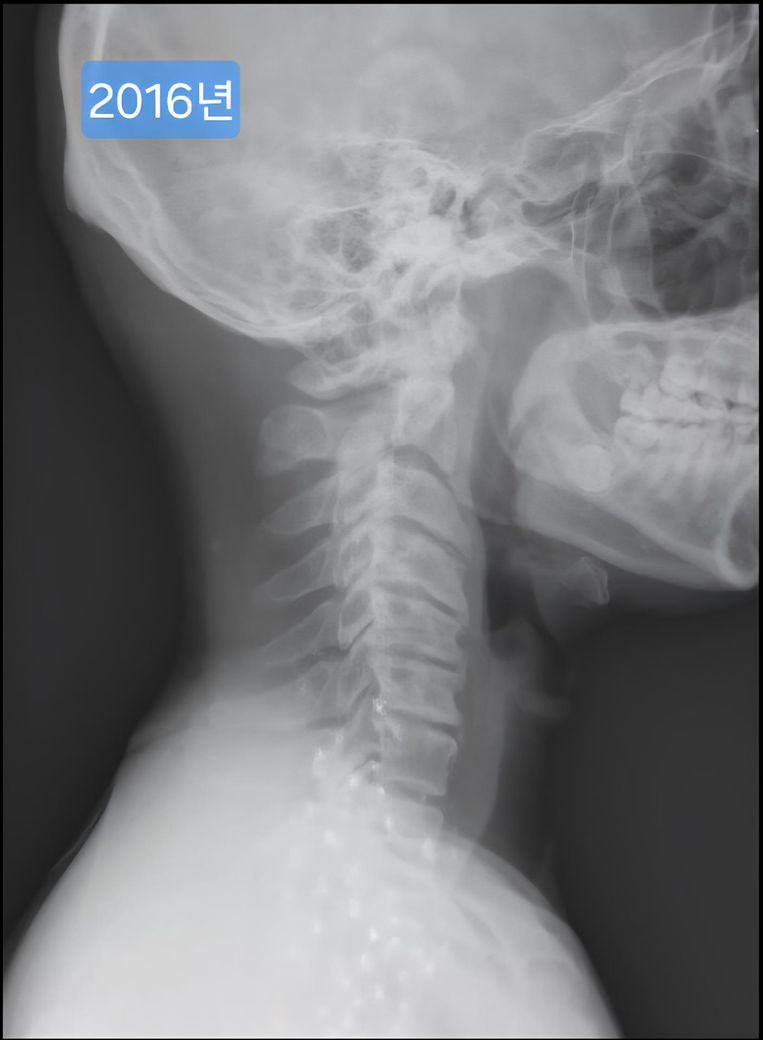

한 9년전에 이때도 운동하다가 어깨가 아파서 목과 어깨 엑스레이를 찍은 자료가 있더라구요.

며칠전 찍은 2025년도 엑스레이와 9년전 사진을 업로드 해 드리겠습니다.

(이미지에 좌측상단에 해당연도 표시했습니다.)

• 3번 째 사진